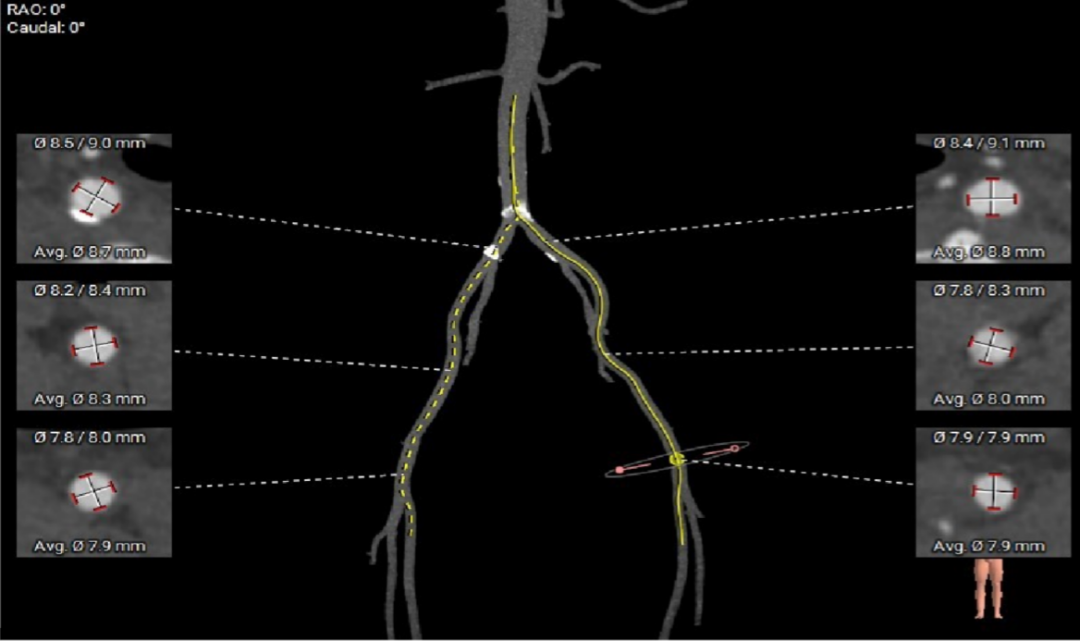

● 外周入路走行适宜,腹主中下端和左右髂总散在钙化,血管内径尚可,血管内壁存在不规则纤维增厚和钙化斑。

外周血管及主动脉弓解剖

术前考虑右侧股动脉为主入路,左侧为辅助入路。非横位心,主动脉弓角度、宽度尚可,预估输送器过弓难度适宜,跨瓣难度适宜,术中必要时采用Snare辅助。左右冠脉开口高度可,左冠切线角度测量瓣叶大于LCA开口下缘到根部距离,结合瓦氏窦及STJ尺寸预估,冠脉风险适中,建议术中密切关注左冠灌注情况。外周入路走行适宜,腹主中下端和左右髂总散在钙化,血管内径尚可,血管内壁存在不规则纤维增厚和钙化斑,入路穿刺规范操作,小心通过,避免入路血管损伤及相关并发症。重度钙化二叶式病变重度主动脉瓣狭窄,其瓣口面积小,瓣口限制明显,术中瓣膜锚定难度较大,瓣膜植入受二叶瓣瓣叶及团块状钙化挤压存在移位及少量偏多瓣周漏风险,为避免手术并发症,手术预装AV26瓣膜,根据20mm球囊预扩结果选择瓣膜型号,计划瓣膜瓣上3mm开始释放。